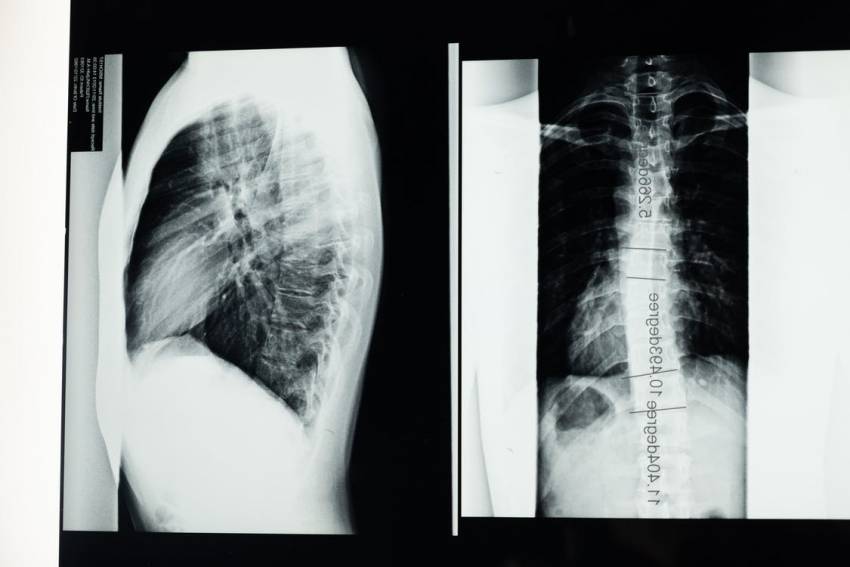

In particolare la Spondilolistesi e le deformità vertebrali. Per Spondilolistesi si intende uno scivolamento di una vertebra sull’altra di natura congenita o acquisita. Caratterizzata clinicamente da dolore lombare, sciatalgia e in casi rari deficit neurologici agli arti inferiori. Le deformità vertebrali neuromuscolare sono patologie vertebrali secondarie a malattie del sistema nervoso centrale e dell’apparato muscolare. Si tratta di deformità che nella maggior parte dei casi colpiscono l’infanzia e l’adolescenza, che costringono i pazienti in carrozzina e che quando particolarmente evolutive possono determinare non solo una poco confortevole posizione seduta e complicare quindi la gestione clinica dei pazienti oltre che un grave deficit cardio respiratorio, compromettendo anche la vita stessa dei pazienti. Entrambe le patologie necessitano di interventi chirurgici tempestivi e particolarmente indaginosi.

In Hesperia Hospital a Modena vi è un centro specializzato presieduto dai Prof.Stefano Cervellati e Matteo Palmisani, che applica la chirurgia mininvasiva per questo tipo di patologie, su pazienti particolarmente gravi, sui quali non è possibile intervenire con il metodo standard.

Inoltre, in Hesperia Hospital, tutta la chirurgia vertebrale si giova dell’utilizzo di tecniche altamente innovative, come la neuronavigazione, la robotica, l’impiego della tac intraoperatoria e del controllo delle funzioni neurologiche durante l’intervento.